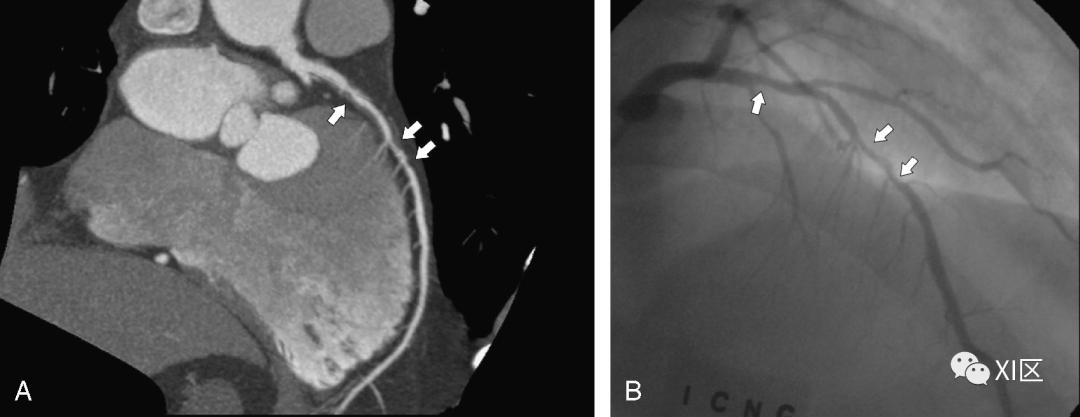

一些研究甚至发现,如果不使用硝酸甘油进行的冠脉CTA检查,有可能出现误诊,如下图的几个病例。

A、 未经硝酸甘油注射的MSCT显示RCA无明显明显狭窄。B、 常规冠状动脉造影显示RCA近端(如箭头所示)存在明显的狭窄,未使用硝酸甘油的MSCT未能发现。